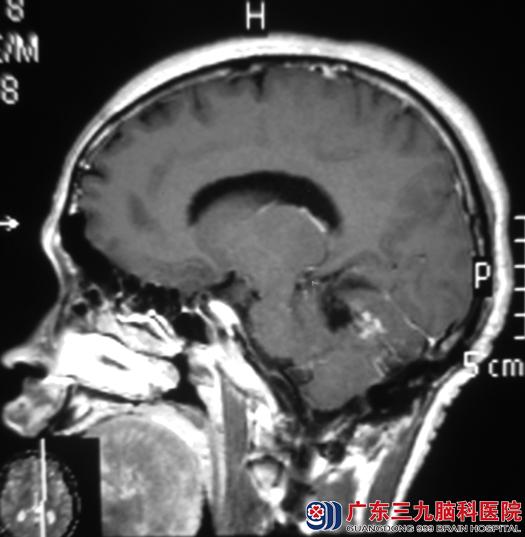

广东三九脑科医院MR检查提示:右侧小脑半球占位性病变,以囊性为主,增强明显,考虑血管母细胞瘤的可能性大。

手术前